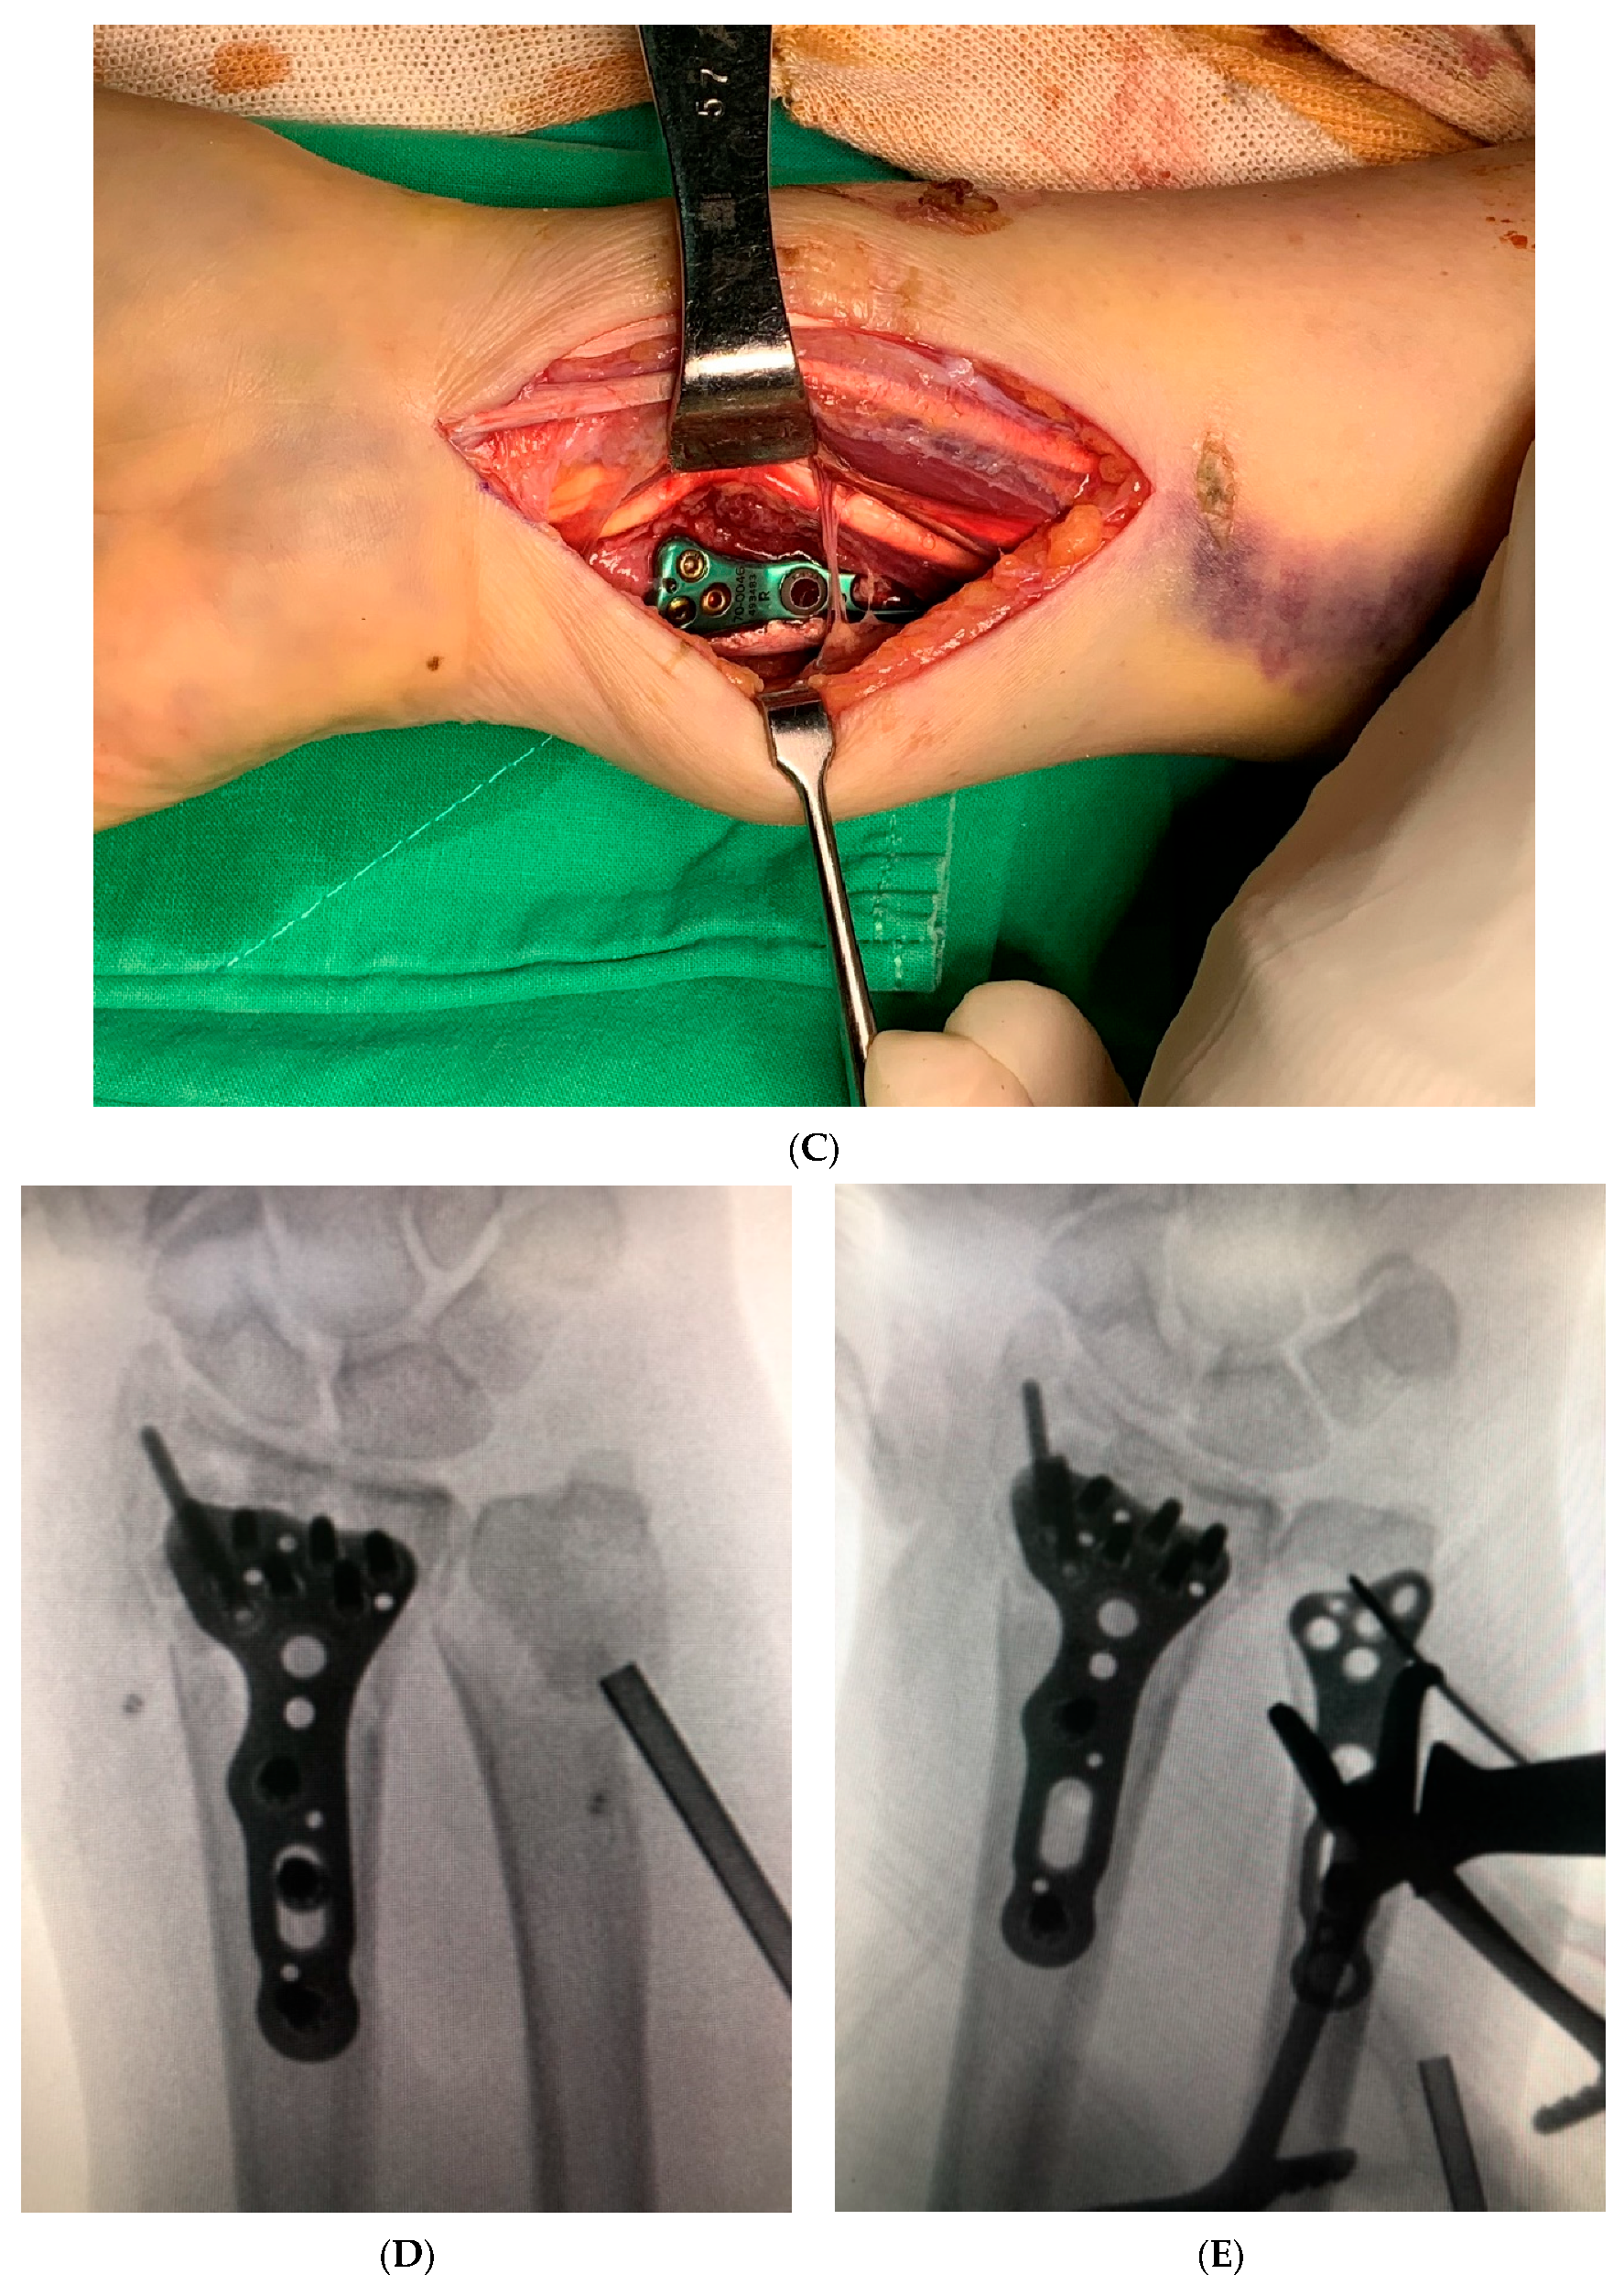

Figure 3.

The figure shows the repair of the pronator quadratus muscle back to the ulna and then to the radius through two surgical windows. (A) lateral window, (B) medial window.